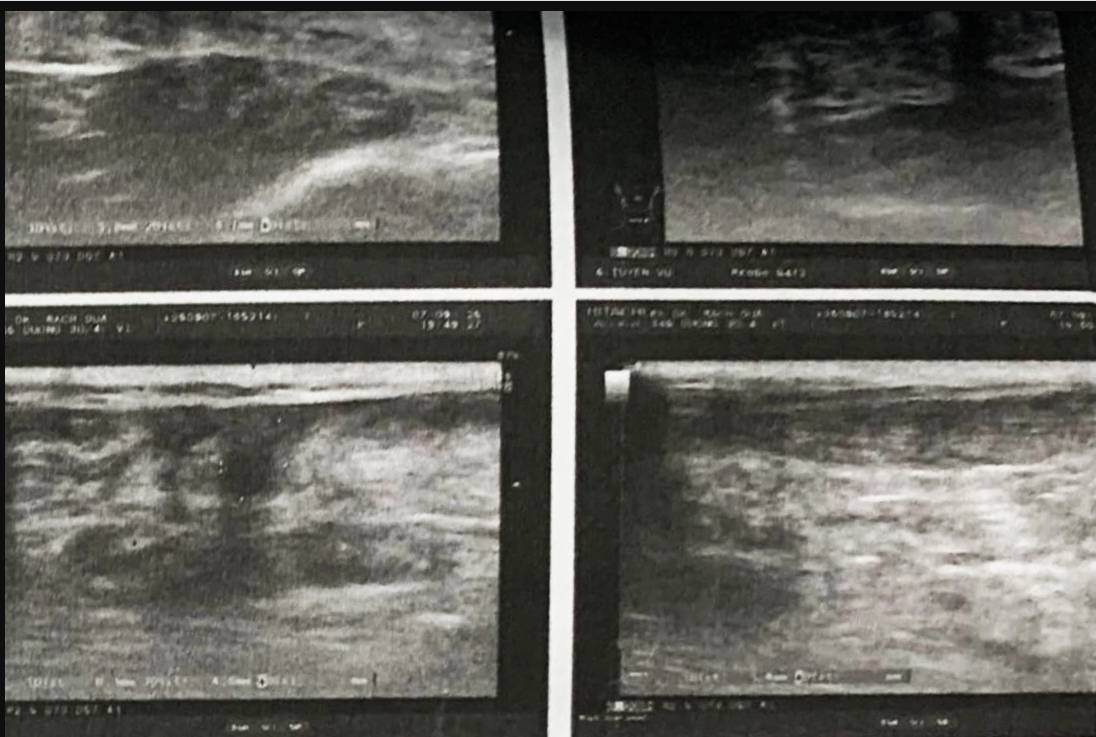

Ảnh chụp chiếu ghi nhận bệnh nhân đứt hoàn toàn gân gót (Ảnh: BS).

Trường hợp thứ hai là một người đàn ông vừa chơi tennis xong thì chuyển sang chơi pickleball. Bệnh nhân cũng nghe âm thanh lạ và bị đau khi dậm chân cứu bóng. Kết quả chụp chiếu hình ảnh cho thấy, bệnh nhân đứt hoàn toàn gân gót, cần phải mổ nối gân.